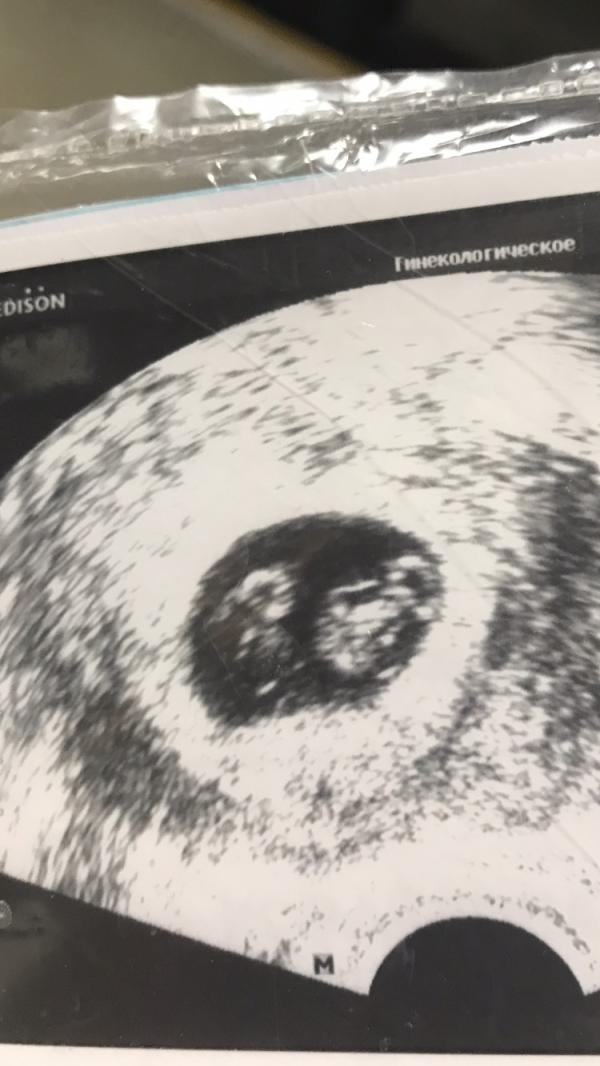

Вспомнила как первый привет получила от малыша на 3дпп. Сделав узи узнала о двойни был большой шок. А сегодня нашим булочка пять месяцев.❤️❤️❤️